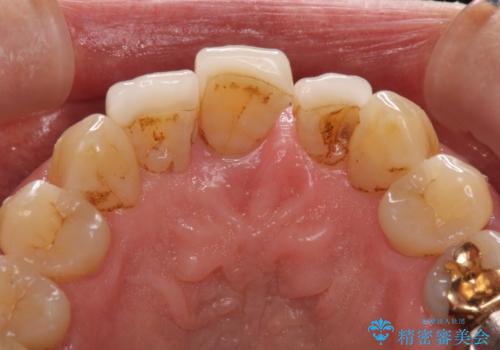

- 上の前歯が痛むとのことで来院された患者様です。

検査を行ったところ、前歯1本は周辺の骨が失われており、抜歯が必要でした。

上顎の奥歯は全体的に歯周ポケットが散見され出血が認められたため、歯周外科処置を行うこととしました。

また、前歯の部分矯正も希望されたため、歯周外科処置と平行して矯正治療を行うこととしました。